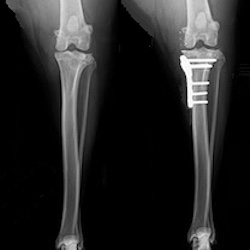

TPLO Caudocranial X-ray

Caudocranial projection post-TPLO